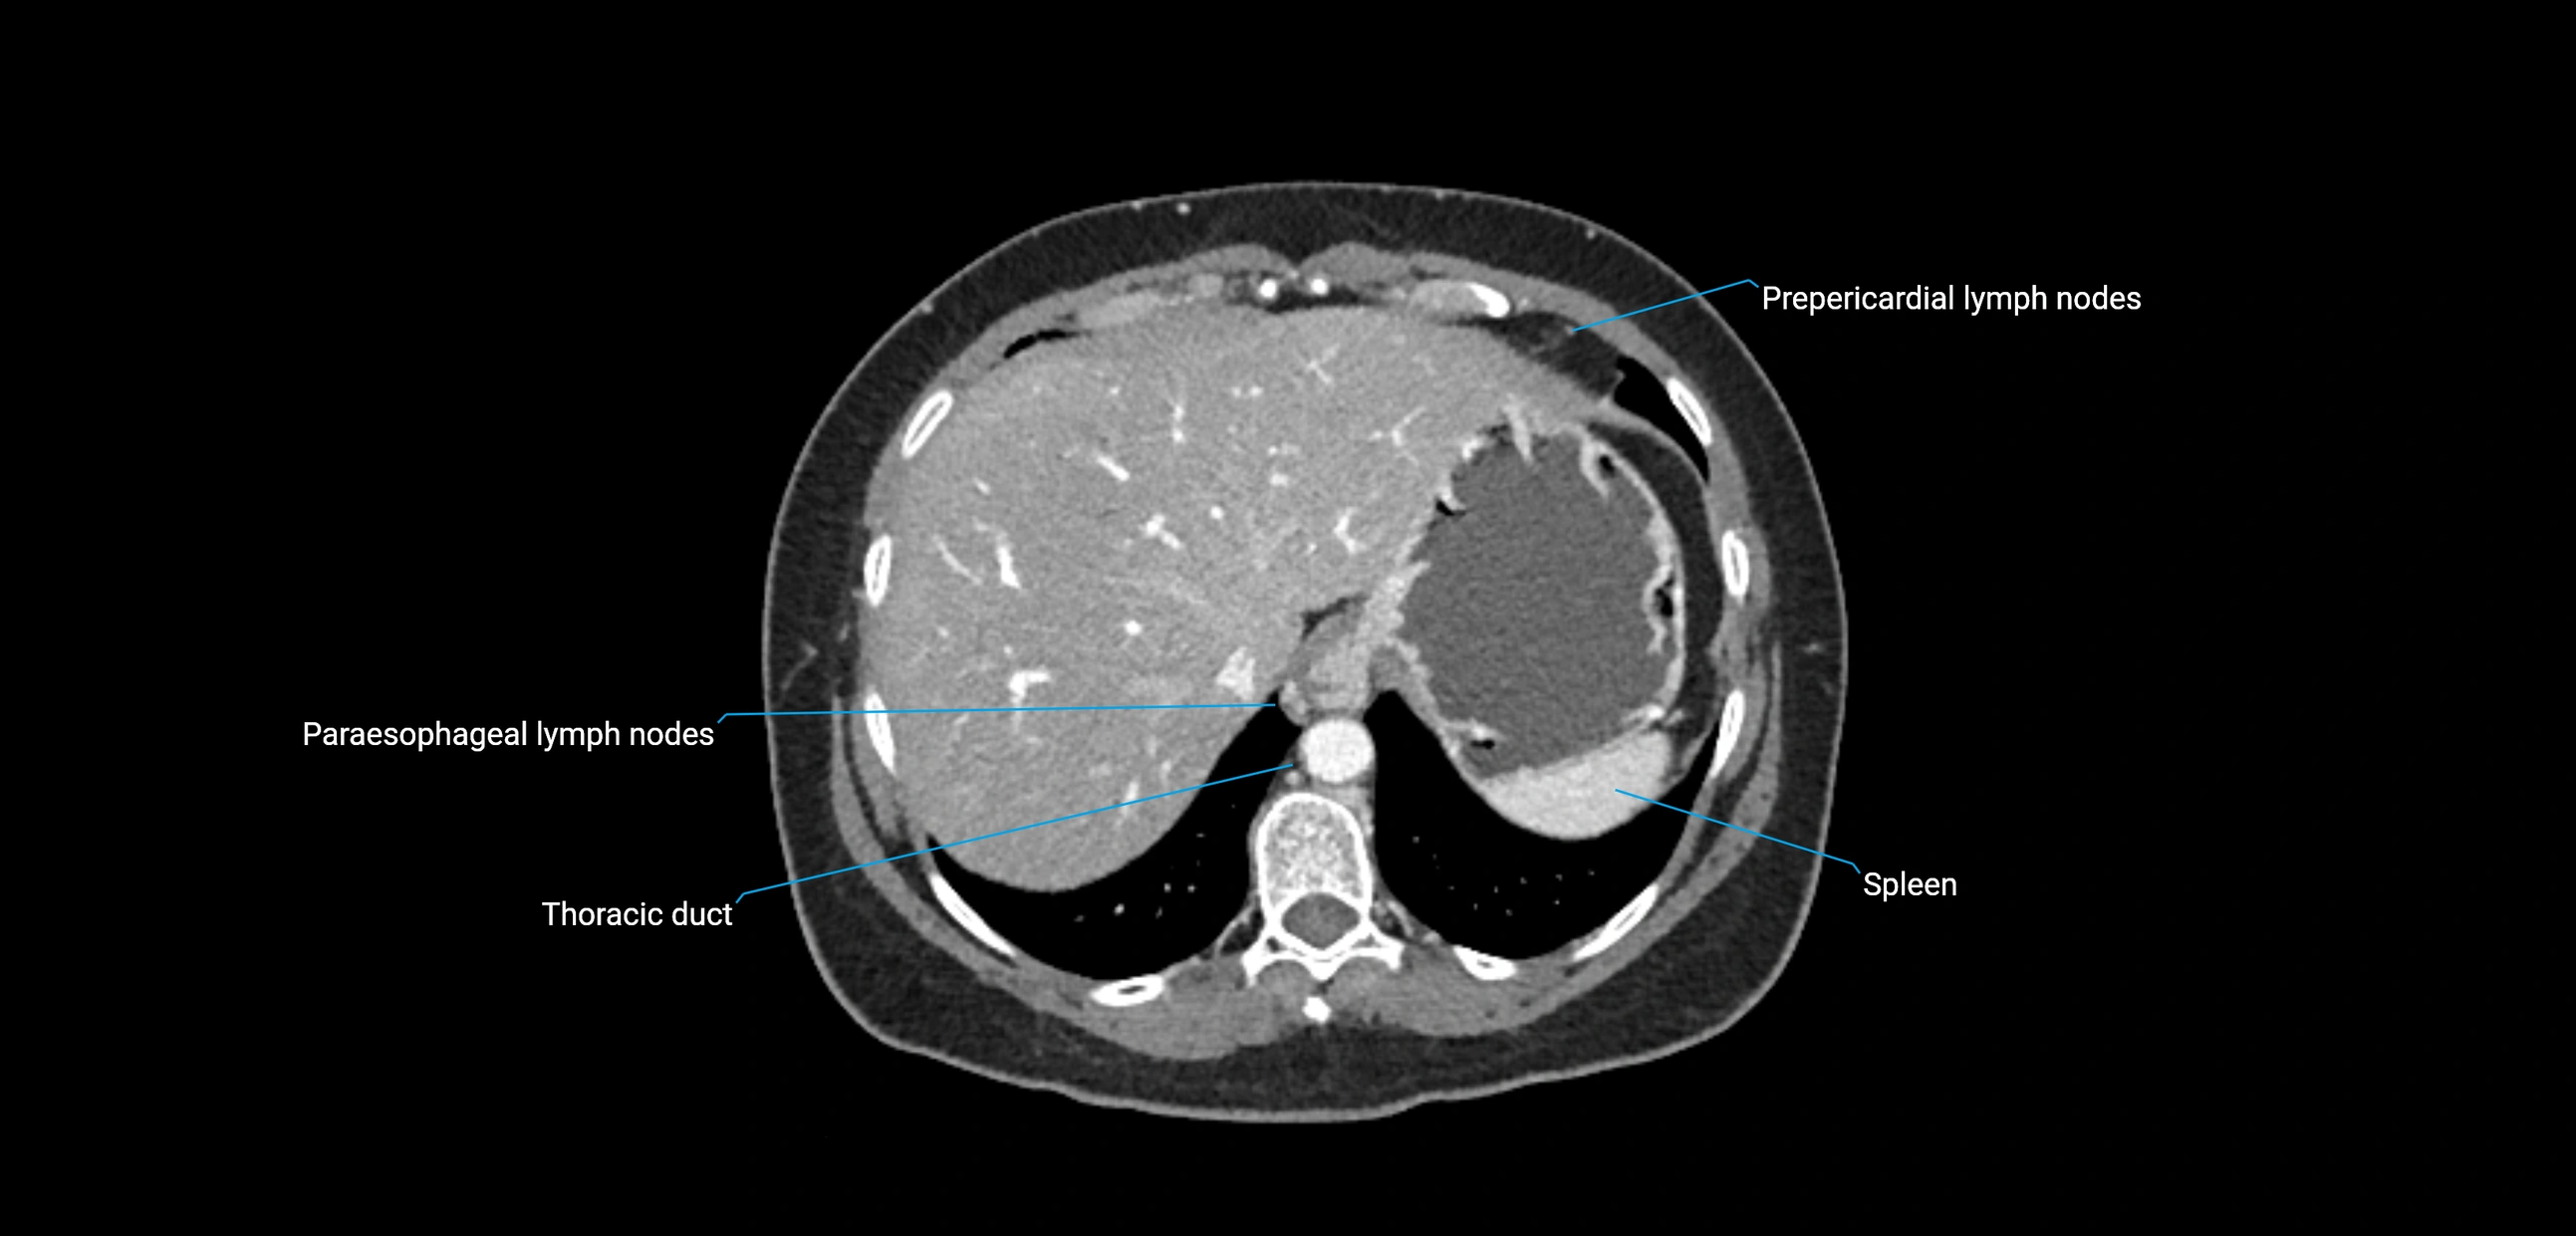

CT Appearance

CT Pre-Contrast:

• Nodes appear as soft-tissue density nodules adjacent to the aorta and IVC

• Calcification may be seen in chronic infections (e.g., tuberculosis)

CT Post-Contrast:

• Normal nodes enhance homogeneously

• Malignant nodes may show heterogeneous enhancement, central necrosis, or conglomerate formation

• Size >1 cm short axis is suspicious, though morphology and distribution are equally important